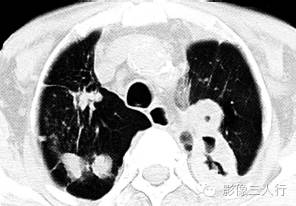

A.B.CT平扫示两上肺多发结节状、片状实变影,左上肺实变影内可见多发空洞,洞壁较厚,内外壁尚光整。纵隔内多发中小淋巴结影;

C.D.肺窗病灶边缘可见长毛刺影,周围可见斑片、条索状影。 医学百科网 | YxBaike.Com

2.两上肺多发结节状密度增高影,结节灶周围可见斑片及条索状影,符合浸润性肺结核多种性状病灶影共存的特征。 医学百科网 | YxBaike.Com

3.结节灶周围粗长毛刺影提示炎性病灶。 医学百科网 | YxBaike.Com

4.肺实变灶内多发大小不一的空洞影是结核性空洞特点之一。 医学百科网 | YxBaike.Com